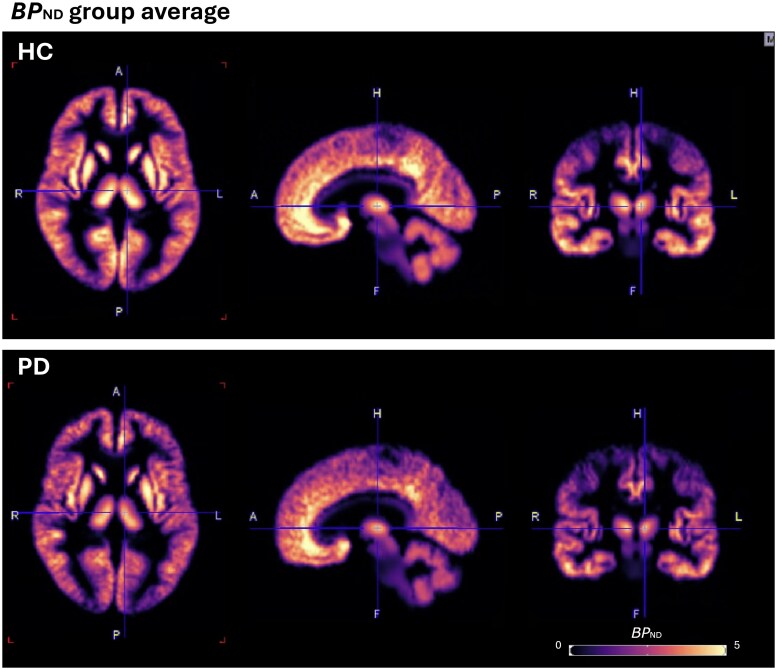

[18F]SynVest-1放射性示踪剂靶向突触囊泡糖蛋白2A (SV2A),是突触前密度的代表。帕金森病与突触功能障碍有关。在这里,我们通过[18F]SynVest-1放射性示踪剂与健康对照比较PD患者的突触密度,并参考其与先前的SV2A放射性示踪剂[11C]UCB-J的比较。10名帕金森患者和12名健康受试者进行了[18F]SynVest-1 PET扫描。我们通过体素分析和兴趣量分析比较了不可置换结合电位,以调查组间差异。兴趣量分析报告了与帕金森病相关的关键先验区域,即黑质和尾状核的不可置换结合电位较低(P < 0.05)。随访探索性兴趣量分析报告,所有脑叶、小脑、海马、丘脑和脑岛的不可置换结合电位普遍降低;然而,这些发现在多次比较后都无法校正(P < 0.004)。此外,具有家族误差校正的体素分析强调了PD队列中壳核和小脑内的不可置换结合潜力显着降低。我们没有观察到临床指标和不可置换结合电位之间的任何关系。结果与使用[11C]UCB-J放射性示踪剂观察到的差异一致。[18F]SynVest-1放射性示踪剂证实帕金森病队列中突触密度较低,并为帕金森病病理中突触功能障碍提供了越来越多的证据。

The [18F]SynVest-1 radiotracer targets the synaptic vesicle glycoprotein 2A (SV2A) and is a proxy of presynaptic density. Parkinson's disease is associated with synaptic dysfunction. Here we investigated synaptic density via the [18F]SynVest-1 radiotracer in people with PD compared with healthy controls, with reference to how it compares to the previous SV2A radiotracer, [11C]UCB-J. Ten Parkinson's patients and 12 healthy subjects underwent a [18F]SynVest-1 PET scan. We compared non-displaceable binding potential via voxel-wise and volume of interest analysis to investigate group differences. Volume-of-interest-analyses reported lower non-displaceable binding potential in key a priori regions associated with Parkinson's disease, namely the substantia nigra and caudate nucleus (P < 0.05). Follow-up exploratory volume-of-interest-analyses reported widespread reduction in non-displaceable binding potential within all brain lobes, cerebellum, hippocampus, thalamus and insula; however, these findings did not survive correction for multiple comparisons (P < 0.004). In addition, voxel-wise analyses with family-wise error correction, highlighted significantly lower non-displaceable binding potential in the PD cohort within the putamen and cerebellum. We did not observe any relationships between clinical metrics and non-displaceable binding potential. The results are in line with differences observed using the [11C]UCB-J radiotracer. The [18F]SynVest-1 radiotracer confirmed lower synaptic density in the Parkinson's disease cohort and adds to the growing evidence of synaptic dysfunction in Parkinson's disease pathology.